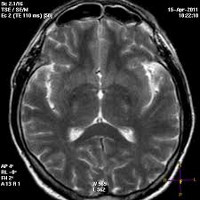

Первичная диагностика энцефалопатии осуществляется неврологом по результатам опроса и неврологического осмотра. Дополнительно проводится комплексное инструментальное неврологическое обследование: электроэнцефалография, эхоэнцефалография, реоэнцефалография или УЗДГ сосудов головы. ЭЭГ, как правило, выявляет диффузную дезорганизацию биоэлектрической активности мозга с появлением медленных волн. Возможно выявление эпи-активности. Эхо-ЭГ позволяет оценить внутричерепное давление. Сосудистые исследования дают информацию о состоянии церебрального кровообращения. Проанализировать степень морфологических изменений можно при помощи МРТ головного мозга. Этот метод также позволяет дифференцировать энцефалопатию от других церебральных заболеваний: болезни Альцгеймера, внутримозговой опухоли, энцефалита, рассеянного энцефаломиелита, инсульта, кортикобазальной дегенерации, болезни Крейтцфельдта - Якоба и пр.